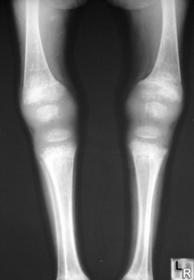

What disease is this? What are the signs of this? | Osteogenesis imperfecta (“Brittle bone disease”) Diffuse cancellous osteopenia (coarse primary trabeculae), diminished tubular bone girth |

What disease is this? | Osteogenesis Imperfecta |